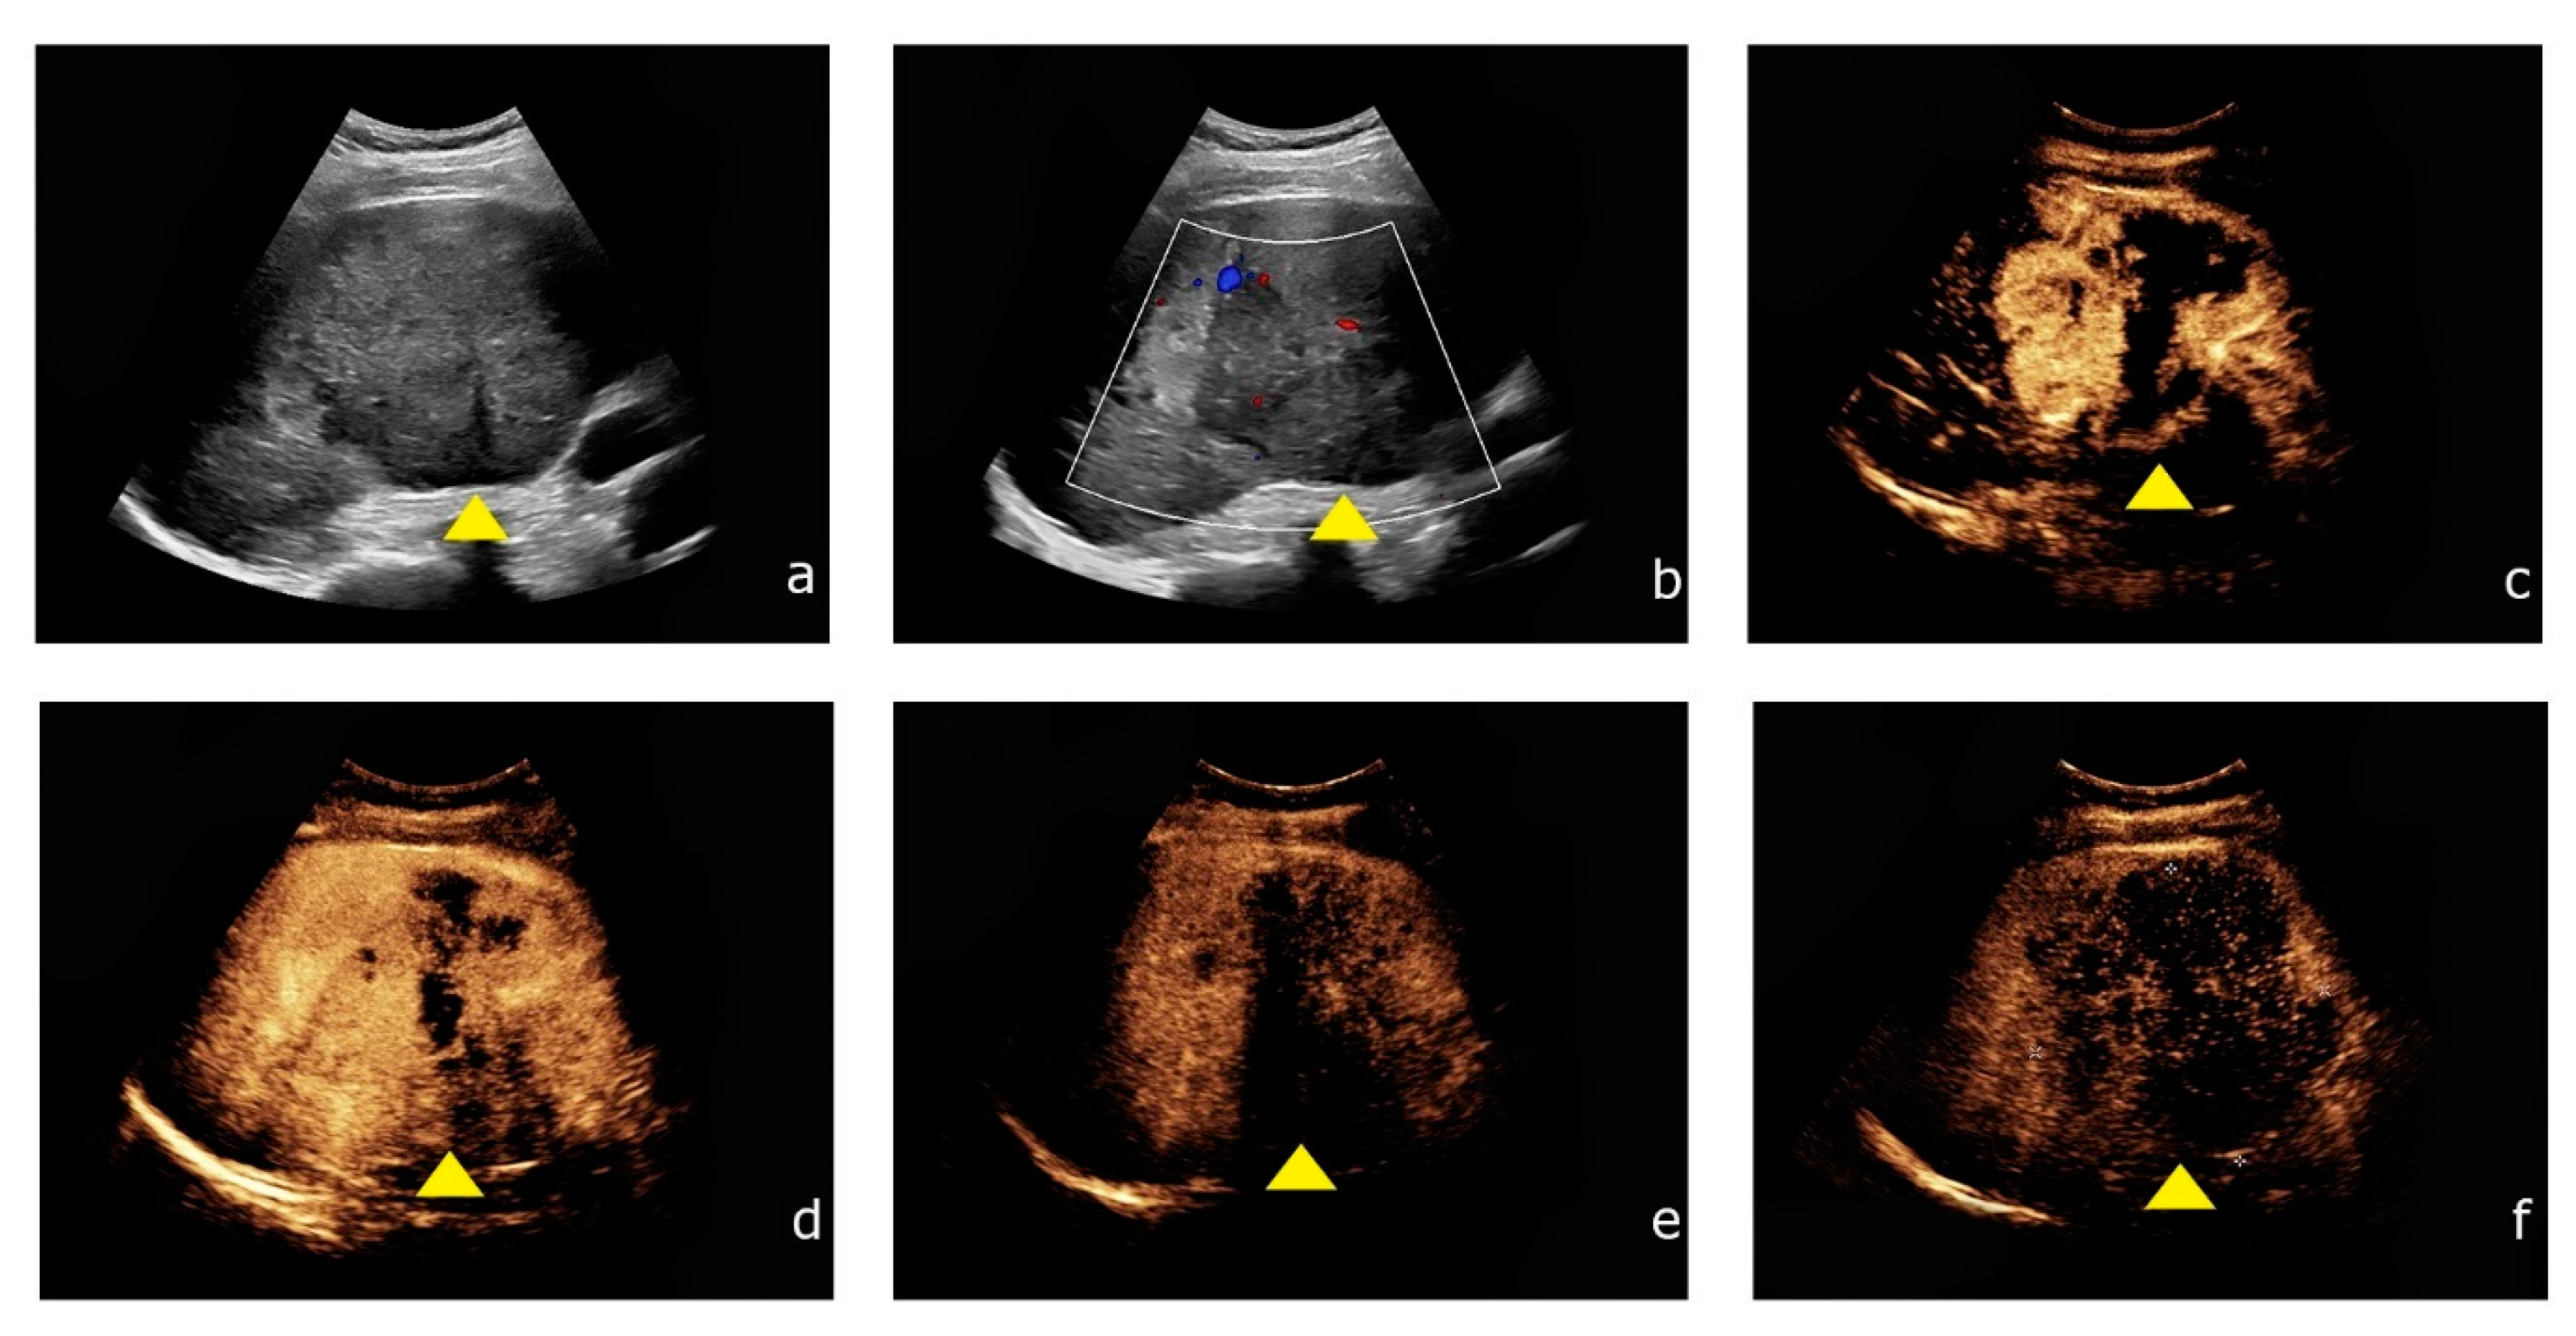

Figure 2. Contrast-enhanced ultrasound of HCC showing the typical contrast enhancement pattern. (a) Inhomogeneous liver lesion (yellow arrowhead) in the right liver lobe (8.7 cm) in native B-mode. (b) Intralesional hypervascularization is detected by Color Doppler. (c,d) After intravenous application of SonoVue® (Bracco, Milan, Italy) the lesion shows rapid contrast enhancement during the arterial phase. (e,f) During the venous phase, the lesion shows typical wash-out during the venous phase.

2.3. Image Acquisition